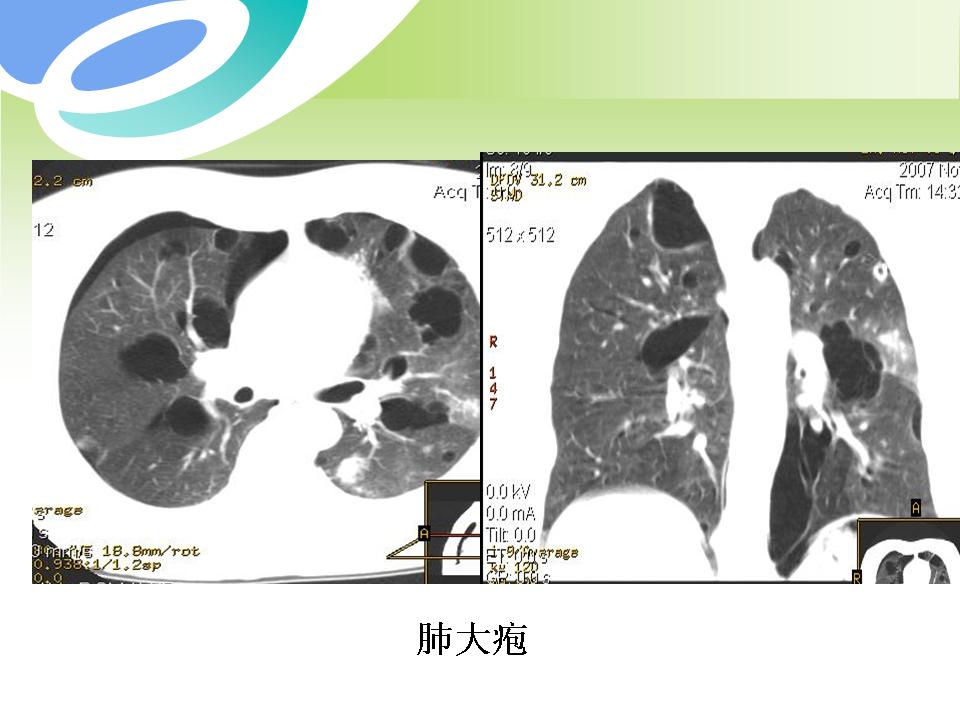

肺部病变的CT基本征象